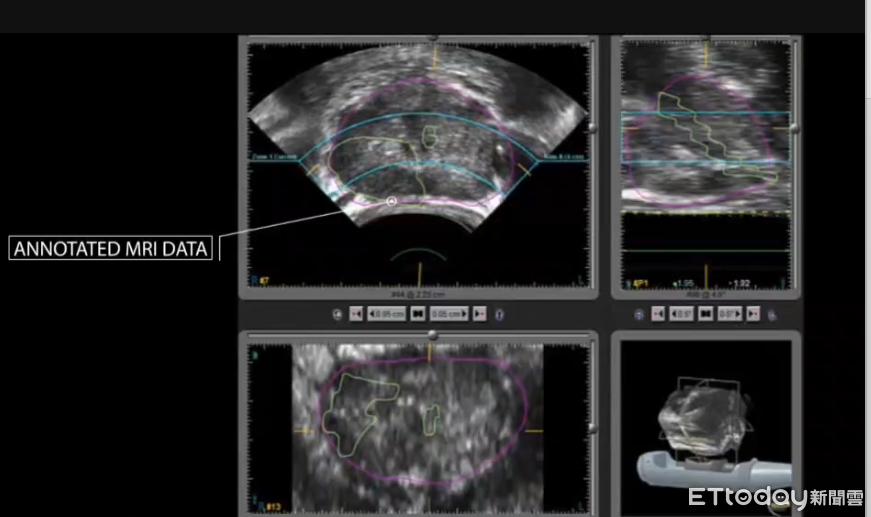

去年,77歲的高先生因下腹悶痛至診所就醫,檢查發現攝護腺癌指數(PSA)達5.78 ng/mL,正常值為4 ng/mL以下,進一步轉診至屏基泌尿科。經過核磁共振檢查與影像融合切片,確認攝護腺內有兩處中度惡性病灶。經由泌尿科主任錢家陞醫師評估後,決定以海福刀為其進行無創治療。

除了技術上的優勢,屏基此次引進的「海福刀」系統更搭載人工智慧(AI)導航與影像融合技術,能準確辨識腫瘤位置與範圍,避免傷及周邊健康組織,進一步提高治療精準度與安全性。